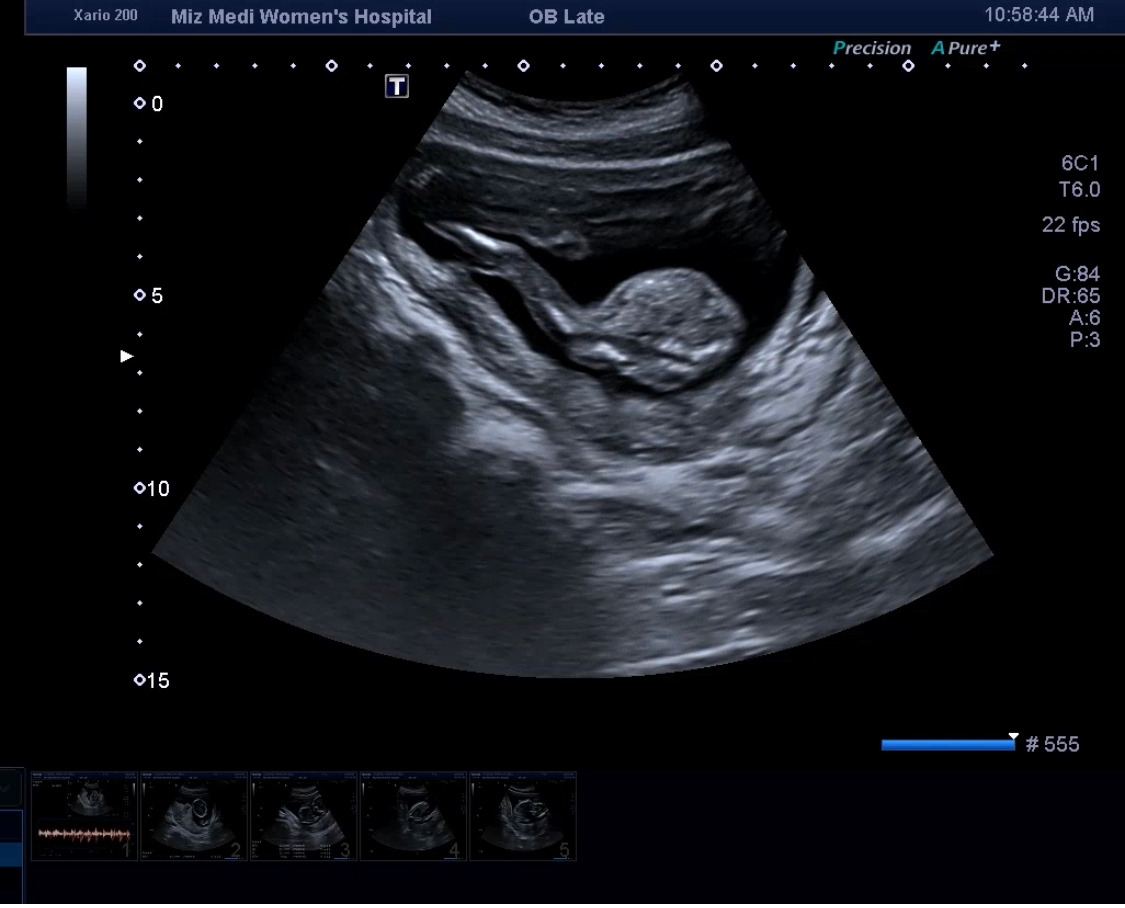

의사 선생님께서 영상을 보여주시는데 우리 다올이가 정말 세상 불편하게 몸을 굽히고 있더라 그래서 이곳저곳 보고 얼굴 보는 게 조금 힘들고 그랬다. 그러다가 선생님이 조금 눌러서 그런가? 불편한 자세에서 다리를 슈욱~ 피더라. 이런 모션 하나하나가 얼마나 귀엽던지..

그리고 다리는 왜 이렇게 길어 보이는지.. 내 새끼라 그런 거겠지.

우리 다올이가 이쁘게 건강하게 잘 태어나면 좋겠다. 엄마 아빠는 다올이를 만나는 그날까지 항상 설레고 기다림이 가득한 시간을 보내고 있단다.